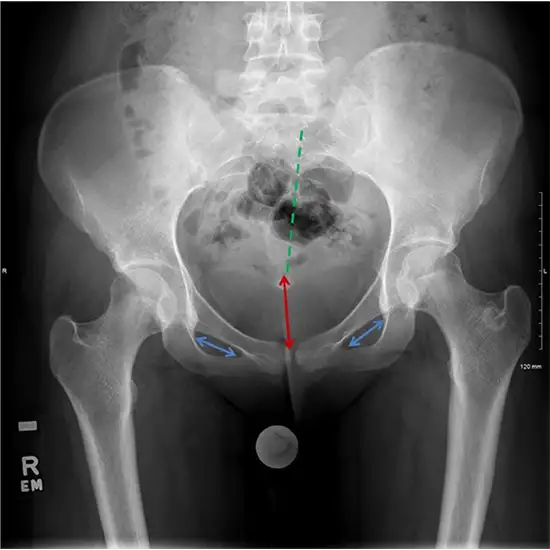

The Hip X-ray procedure examines the pelvis, consisting of three bones: pubis, ilium, and ischium. The scanned picture is black and white and depicts the bones and tissues of the scanned body component. The anteroposterior (AP) view is the view of the hip from the front. The exam often includes scanning both hips for improved results interpretation.

Hip X-ray examinations are used for the following reasons: To identify various medical disorders, including hip arthritis, pelvic fractures, tumors, and hip dislocations. Diagnosing spondylitis and hip region inflammation fractures, cysts, and other related conditions